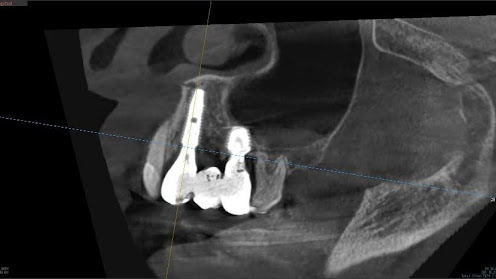

5.左上4番のインプラント抜歯即時埋入、左上6番の上顎既存骨1から2mmのグラフトレスサイナスリフト、左下56の大幅な骨欠損により、下顎神経の損傷を回避するために、ショートインプラントを使用し、左下56にインプラントを埋入し、最終補綴物は、左上456の3ユニットのジルコニアブリッジし、左下56は、ジルコニアの連結冠を装着したケース

Before

枚方市のインプラントの症例

M・I 様 女性 70代

症状としては、左下56は、歯周病で欠損したと考えられるが、かなりの骨欠損をともなっていた。左上456に関しては、動揺が大きく、炎症が起き、排膿、および、歯性上顎洞炎を起こしていた。

治療法としては、動揺がひどくなってきて、炎症の症状もあったため、左上56の抜歯を希望。インプラント治療をその後、希望したため、左上4に関しては抜歯即時埋入。左上6に関しては、既存骨1から2mmでインプラント治療が厳しい状態であったが、グラフトレスサイナスリフトを行い、治療期間5か月はかかるということを説明して、インプラント埋入をおこないました。その後、2か月半後、大幅に骨が欠損している下顎56に対して、ショートインプラントを使用して、下顎神経の損傷を避けて、インプラント埋入を終えています。その後2か月後に光学印象で印象を行い、上顎刺億456歯、3ユニットのジルコニアブリッジを装着。下顎左側56に関しては、骨欠損が大きいため、歯冠長がだいぶ長くなるため、ジルコニアの連結冠を装着して治療を終えた。

治療結果は、上顎6に関しては、既存骨が少なく、厳しい治療ではありましたが、5か月で治療を終え、患者様の負担を最小限に抑えるができたと考えます。(従来のサイナスリフトでは、このようなケースでは1年以上、1年程度の治療期間がかかるか、治療が不可能と言われるケースだと考えます。)また、下顎は骨欠損が大きく、下歯槽管のリスクが起きることが考えられますが、ショートインプラントを使用することで安全に治療を行うことができました。

治療の期間・回数:治療期間5か月(上顎456 3ピースブリッジの治療は5か月(上顎既存骨が2mm程度しかなく、骨結合に時間がかかるケースであったために、5か月の治療期間が必要であった。)(左下56に関しては2か月半で治療を終えています。)治療回数は、13回。

治療の価格:1,474,000円(税込)

治療費の内訳:左上46および左下56のインプラント基本料(フィックスチャー及び手術費用、投薬費用、レントゲン費用、インプラント上部費用(アバットメントおよびジルコニアクラウンの費用用)330000円(税込み)×4本分 1320000円(税込)。左上5ジルコニアポンテック費用88000円(税込)。オプション費用、左上4抜歯即時埋入加算(人工骨費用を含む)+グラフトレスサイナスリフト費用 33000円(税込)、左上6グラフトレスサイナスリフト費用 33000円(税込)

治療のリスクや副作用:手術後に、痛みや腫れ、出血、合併症などを引き起こす可能性があります。噛む感覚がご自身の歯と異なる場合があります。見た目がご自身の歯と異なる場合があります。手術後にメインテナンスを継続しないと、インプラントが抜け落ちる可能性があります。